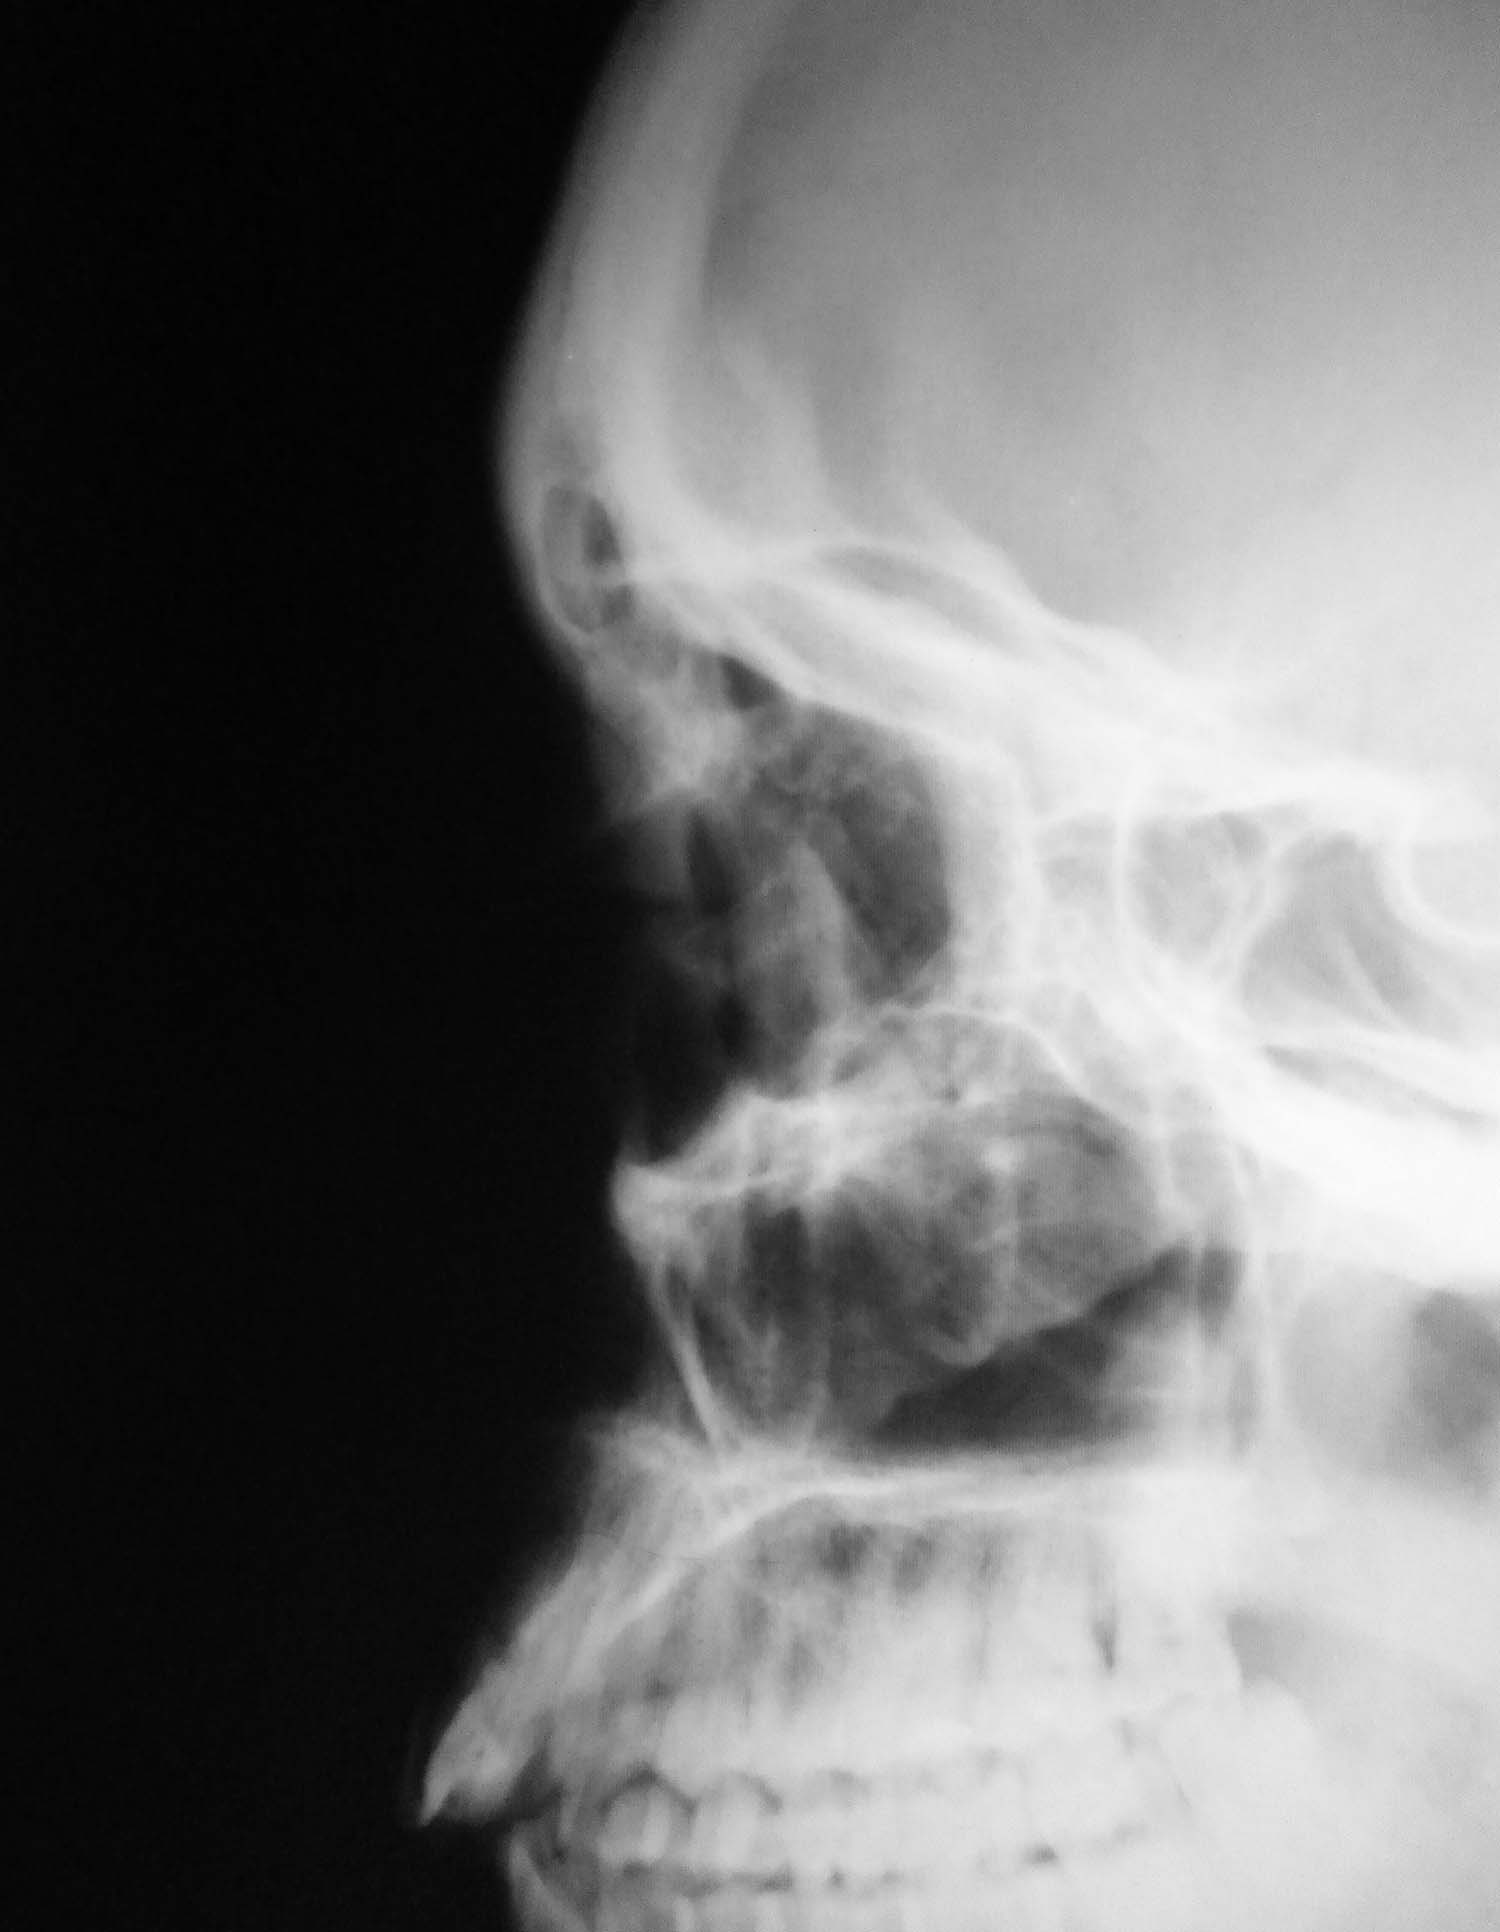

Есть ли интраорбитальная эмфизема?

Женьщина 1983 года рождения, получила удар кулаком в лицо, каторый прошел справа налево, по касательной переносицу, левое глазное яблоко и левую бровь. Внешне слева выраженная параорбитальная гематома. Выполнены рентгенограммы глазниц с интервалом в 2 дня.

Клинически данных за перелом левой глазницы нет. Мне не нравится то что контуры левого глазного яблока такие четкие. Могла ли интраорбитальная эмфизема быть причиной такой четкости контуров глазного яблока? Есть ли она на представленных рентгенограммах? Я подозреваю разрывной перелом стенки левой глазницы, понимаю что КТ может решить этот вопрос, но КТ у нас нет.

Я считаю, что есть.Более выраженная на первом снимке.

А эмфизема слева очень вероятна

Мне кажется, есть. На 1 снимке более выраженная. Воздух, конечно, может быть и под веком, но веко так к носу не уходит.

Эмфизема есть. Вероятнее всего перелом медиальной стенки орбиты. Можно попробовать томограммы, хотя оптимальна КТ.